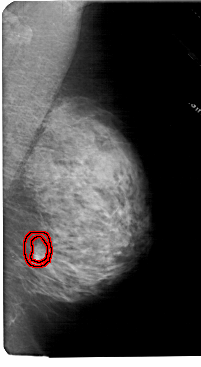

RIGHT_MLO LINES 5491 PIXELS_PER_LINE 3001 BITS_PER_PIXEL 12 RESOLUTION 43.5 OVERLAY

FILE: A_1985_1.RIGHT_MLO.OVERLAY

TOTAL_ABNORMALITIES 1

ABNORMALITY 1

LESION_TYPE MASS SHAPE IRREGULAR MARGINS SPICULATED

ASSESSMENT 5

SUBTLETY 2

PATHOLOGY MALIGNANT

TOTAL_OUTLINES 2

BOUNDARY

CORE